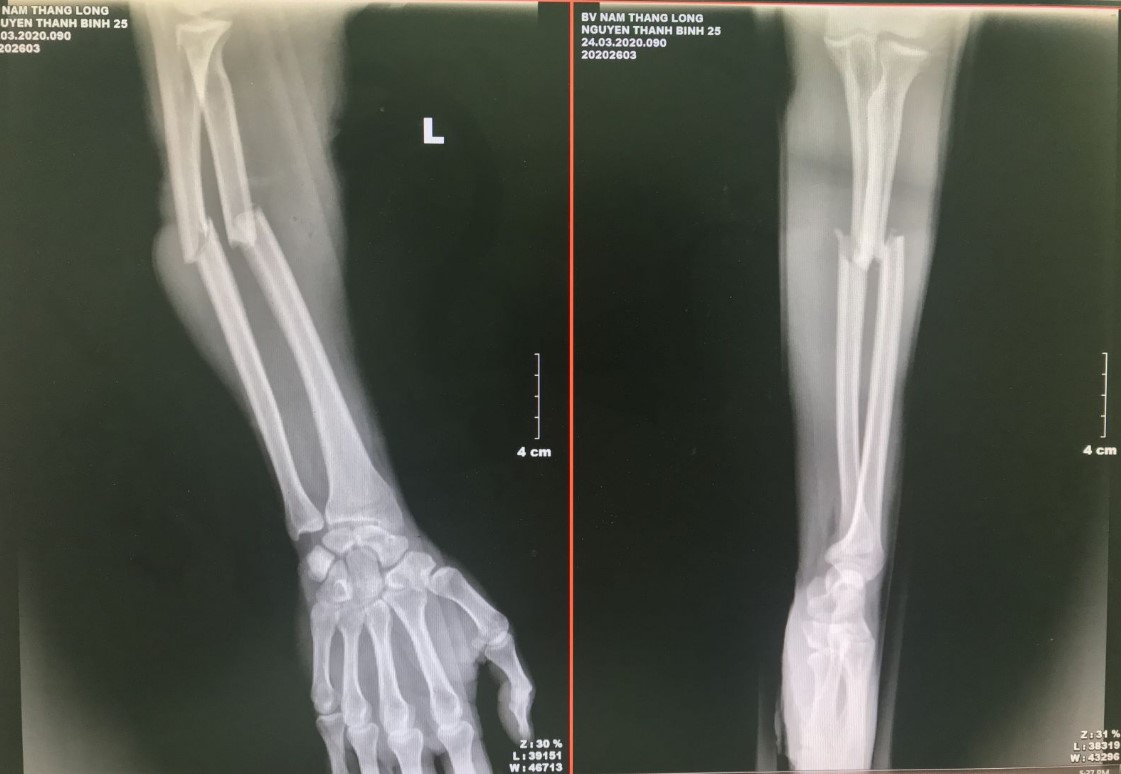

Sơ cứu gãy xương cẳng tay

Đo xương cẳng tay từ 2 cm dưới nếp gấp khuỷu tay đến 5 cm trên nếp gấp cổ tay. Sơ cứu gãy xương cẳng tay bằng cách:

- Bước 1: Cố định cẳng tay bị gãy sát vào thân, cẳng tay vuông góc với cánh tay, lòng bàn tay hướng lên trên.

- Bước 2: Chuẩn bị 2 nẹp, một ở mặt trong của cẳng tay (từ lòng bàn tay đến nếp gấp khuỷu tay) và một ở mặt ngoài của cẳng tay (từ đầu ngón tay đến khuỷu tay).

- Bước 3: Nẹp bàn tay và thân cẳng tay (trên, dưới ổ gãy) bằng garo. Sử dụng một chiếc khăn hình tam giác để hỗ trợ cẳng tay của bạn treo trước ngực.